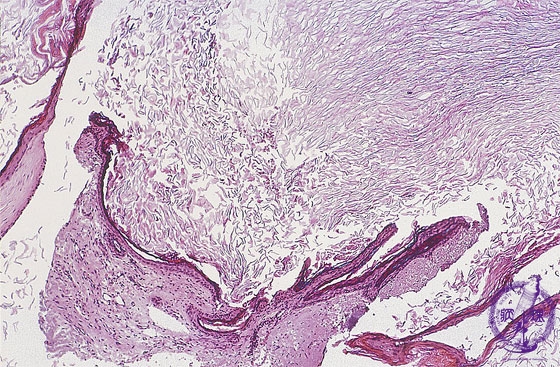

Fragments of keratinizing stratified squamous epithelium are characteristic of cholesteatomas.